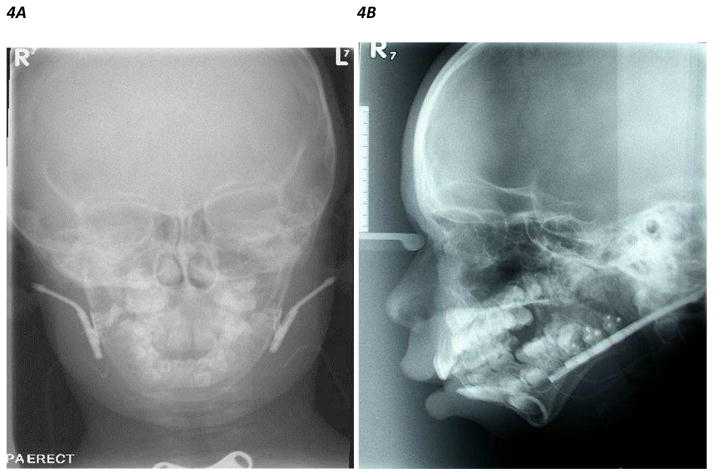

Mandibular distraction osteogenesis (MDO) was initially used as a means of achieving stabilization of the upper airway to enable successful decannulation in older PRS patients with tracheotomies who had previously failed decannulation (99). This technique involves cutting the bone, followed by a lag period during which the callus is allowed to form, before progressively advancing the segments of bone apart controlled on a rigid frame at 1–2mm/day. A consolidation phase then follows, allowing for the distracted soft callus to ossify. The pharyngeal airway size is thus increased by the gradual mandibular lengthening. Use of the technique was then expanded to infants with PRS as an alternative to tracheostomy (100). Once again, this is mainly effective for patients who have obstruction at the level of the tongue base. The distraction devices can be internal or external. External devices are easier to adjust and remove, but can be dislodged, and are associated with scarring. Internal devices tend to be better tolerated, but may require repeat general anesthetics for adjustment and removal (101). Many centers have moved towards internal devices as recent developments have meant that anesthetics for adjustment may no longer be necessary (Figure 4).

Figure 4.

Figure 4A, B. Frontal and lateral skull X ray showing bilateral internal mandibular distraction osteogenesis devices inserted in both mandibles of a patient with mandibular hypoplasia

Figure 4C. Lateral CT scan 3D craniofacial reconstruction images showing internal mandibular distraction osteogenesis device in the left mandibular ramus of a patient with mandibular hypoplasia